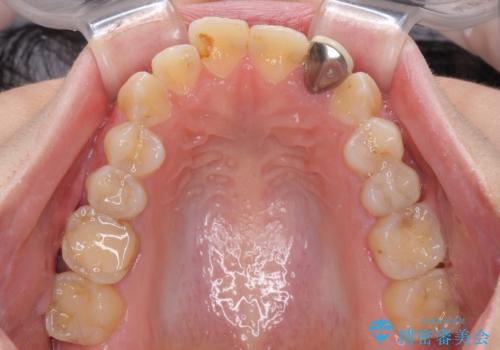

開咬を治す インビザラインによる矯正治療

- 上下前歯の開咬を気にして来院された患者様です。

開咬はインビザラインを用いると有意に改善ができるため、インビザラインによる矯正治療を行うこととしました。

途中1年8ヶ月ほど来院されず、久しぶりの来院後は治療が面倒とのことで、前歯の叢生や隙間に不十分な点が残った状態での終了となりました。